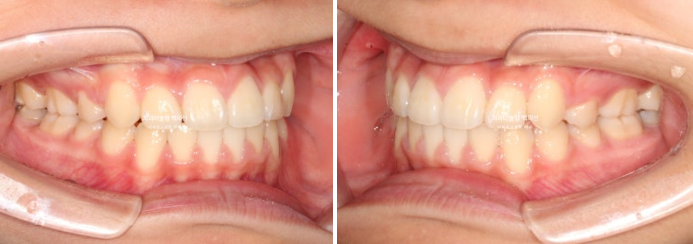

23.02

23년 2월 교정치료를 위해 온 중학생 환자분입니다.

덧니와 중심선 불일치, 과개교합 등이 눈에 띕니다.

덧니가 있으면 덧니쪽으로 중심선이 돌아가게 됩니다.

교정치료로 치아중심선을 코와 인중에 맞춰야 합니다.

앞니 뻗침도 있어서 약간의 돌출입도 있습니다.

덧니와 돌출 해소를 위해 작은어금니 발치교정이 필요합니다.

단 위에만 2개 발치 치료계획을 세워습니다.

아래 작은어금니까지 총 4개를 빼면 입이 너무 많이 들어가게 되기 때문입니다.

클리피씨 교정 선택하셨고 치료 들어갔습니다.

이제 전 후 비교 보겠습니다.

23.02~25.05

총 치료기간은 2년 3개월입니다.

코와 인중이 맞아진 상악 중심선

2mm의 어긋남이 해소가 되어 맞아진 상악과 하악 치아중심선

적절한 입동굴로 아담해진 치열

완만한 U자형의 스마일라인

미소가 훨씬 정돈되고 깔끔한 느낌이 듭니다.